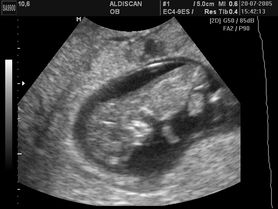

Płód w 9 tygodniu ciąży (zdjęcia)